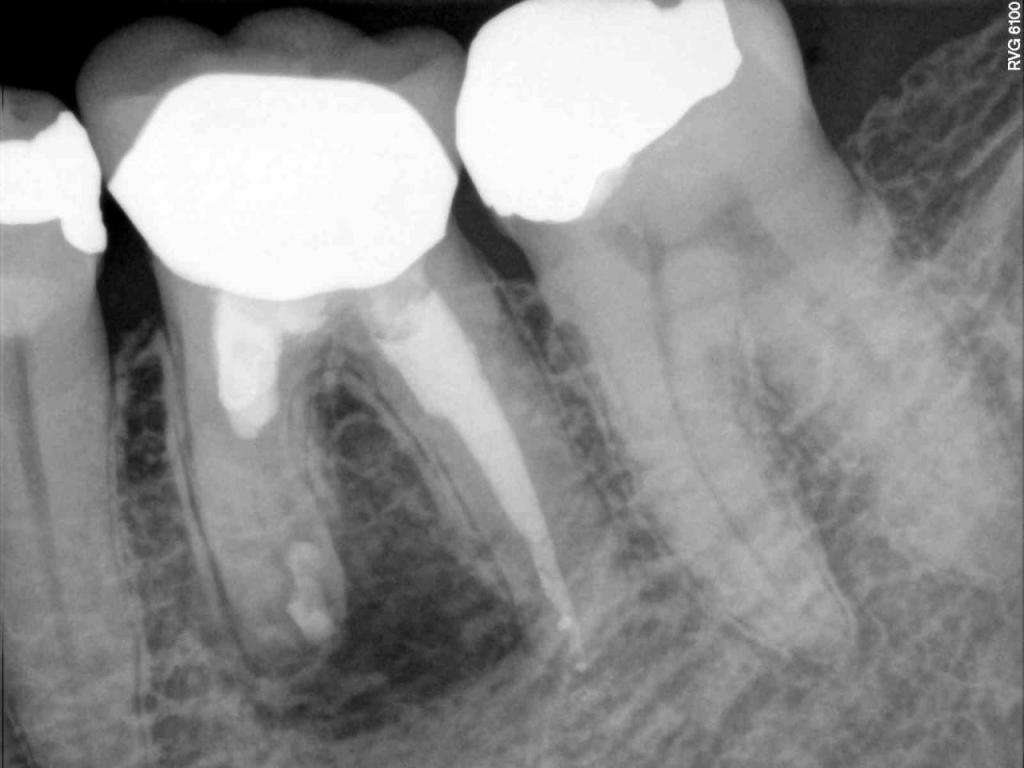

Although the primary use of visual documentation is for patient charts, dental images provide a meaningful way to communicate with patients about their care needs. Digital imagery is a vital tool for educating patients and an essential way to share information with office staff, colleagues and referring doctors. Digital technology has allowed Southcenter Endodontics to enhance our practice and improve the delivery of care to our patients. Below you will see images of “Before” and “After” scenarios. By clicking on a thumbnail image below, you will be able to see and a larger view of the x-ray taken at Southcenter Endodontics and notations made regarding each film.